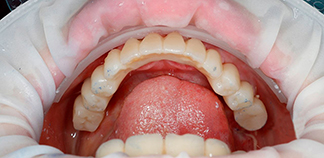

До лечения

Жалоба на отсутствие зубов длительное время.

Пациенту 63 года.

Как лечили

Из-за долго отсутствия нижних зубов и дефицита костной ткани удалены оставшиеся зубы. На нижнюю челюсть установлены четыре импланта и временная ортопедическая конструкция. В дальнейшем будет установлен постоянный протез.

Лечащий врач

БОЙКО Артемий Петрович